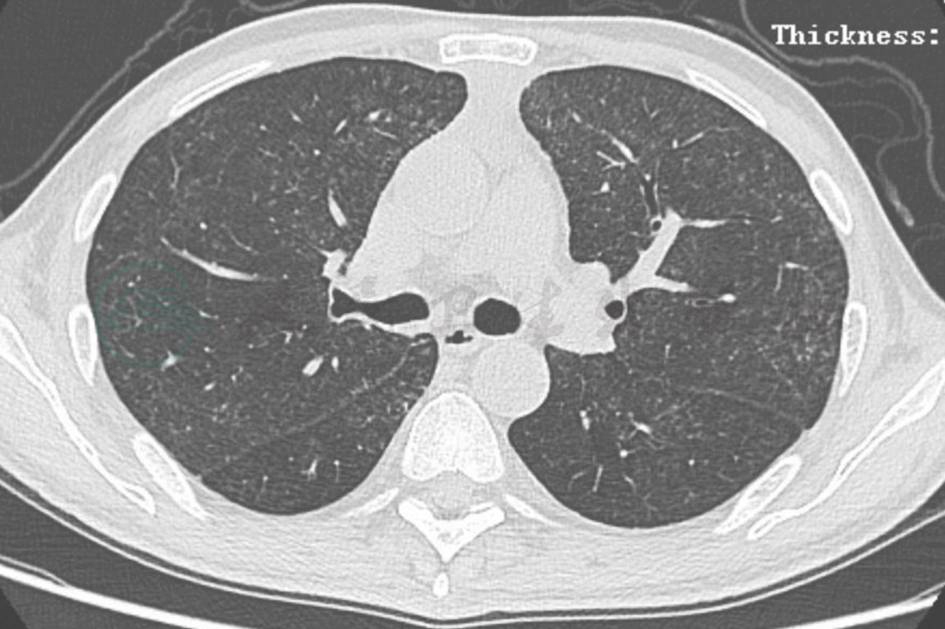

图2 肺泡蛋白沉积症胸部CT表现

男性患者,55岁,因活动后胸闷、气喘5年入院。胸部CT示两肺多发磨玻璃影,地图样分布,其内见铺路石征。行支气管镜检查,支气管肺泡灌洗液及病理符合PAP